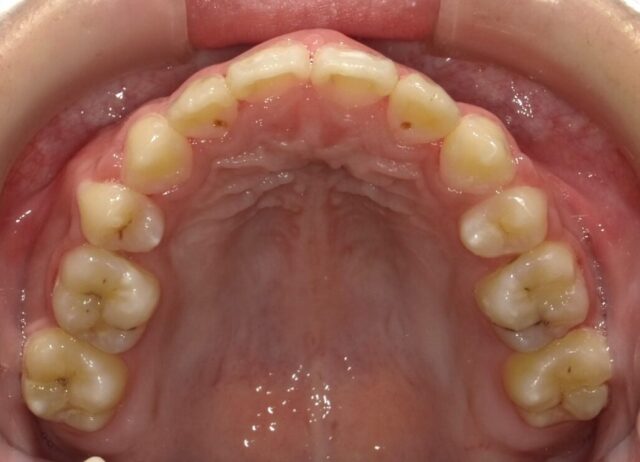

≪上顎咬合面観≫

2023年5月

2023年6月

2023年7月

2023年8月

2023年9月

2023年10月

2023年11月

2023年12月

2024年1月

2024年2月

2024年3月

2024年4月

2024年5月

2024年6月

2024年7月

2024年8月

2024年9月

2024年10月

2024年12月

2025年1月